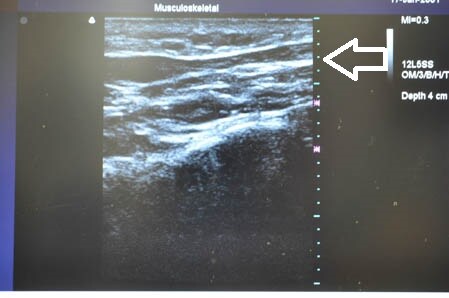

下腹部も同様に。

↓ ↓ ↓